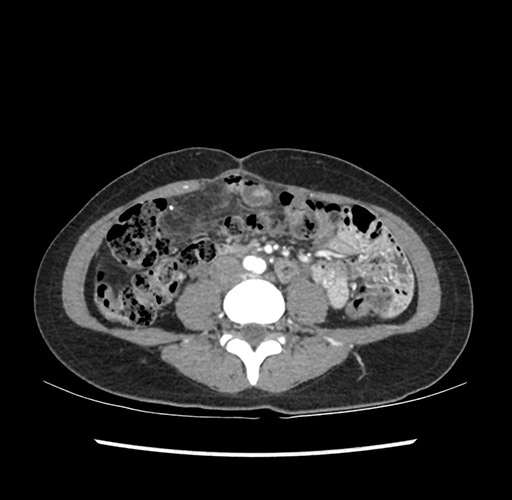

Imaging Analysis

Look through the patient's CT scan to identify any areas of concern for the necessary procedure.

Based on your CT findings, which issue(s) would give reason for "planned slowing down moment(s)" in this case?